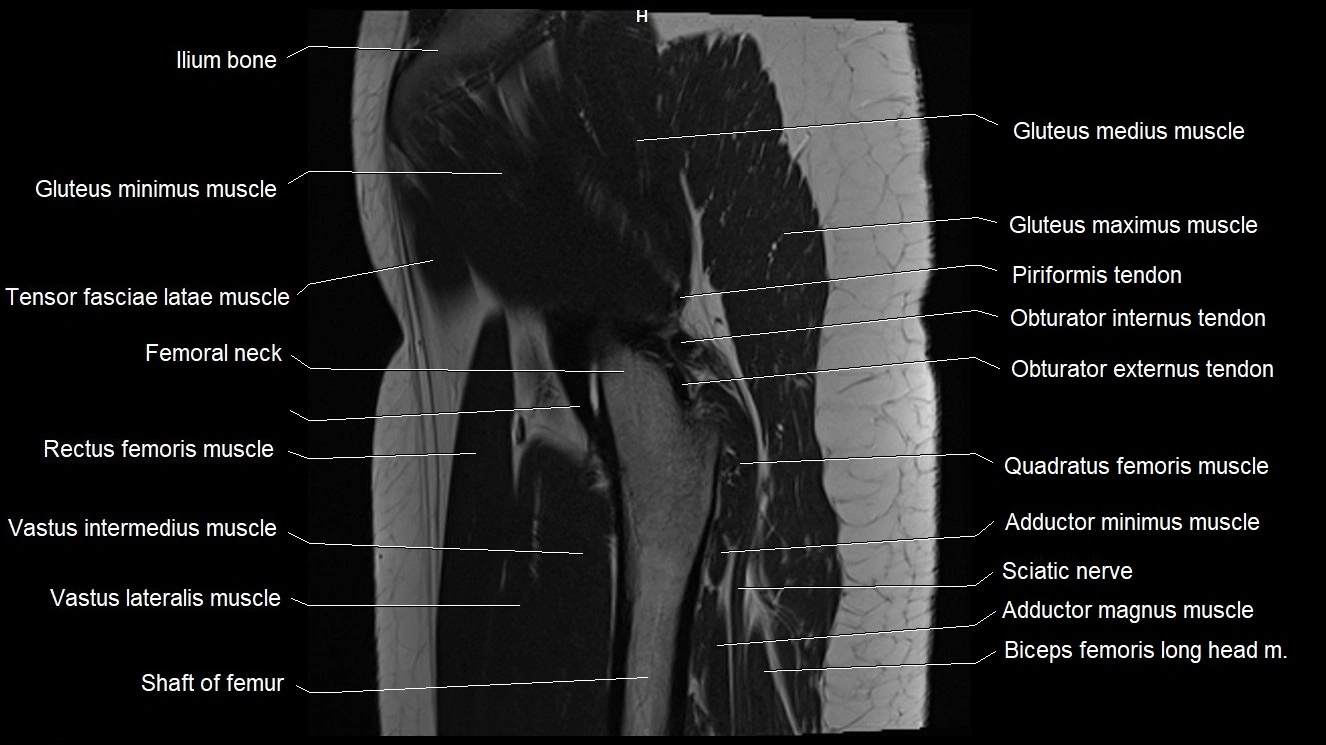

- Gluteus maximus muscle

- Gluteus medius muscle

- Gluteus minimus muscle

- Iliotibial tract

- Ilium bone

- Neck of femur

- Obturator externus tendon

- Obturator internus muscle

- Obturator internus tendon

- Quadratus femoris muscle

- Rectus femoris muscle

- Tensor fasciae latae muscle

- Vastus intermedius muscle

- Vastus lateralis muscle